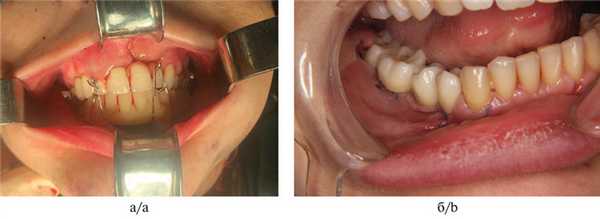

5. Фиксация временных искусственных зубов с опорой на дентальные имплантаты (рис. 5); Рис. 5. Временная конструкция с опорой на дентальные имплантаты в области голени.

6. Аноксия аутотрансплантата. Фиксация аутотрансплантата в реципиентную область с введением искусственных зубов в прикус (рис. 6); Рис. 6. Внутриротовая съемка. а — интраоперационно; б — через 4 сут после операции.